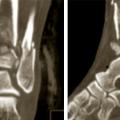

Fracture du pilon tibial

LESIONS PERI-ARTICULAIRES

LESIONS LIGAMENTAIRES

Image